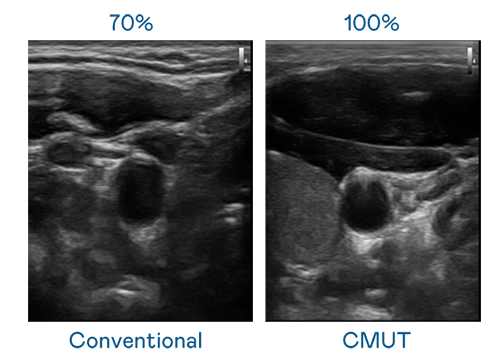

CMUT 技术是一种用电容式微机电元件来产生超音波讯号的技术。与传统 PZT 压电式技术相比,CMUT 频宽增加 30%,更宽频的超音波讯号让影像解析度大幅提升,是实现高影像品质医疗超音波扫描、促进精准医疗发展的关键技术。

大频宽带来超清晰影像

超音波影像的解析度高低,首先取决于探头能发出的讯号频宽。蘑菇视频免费网站入口 CMUT 可提供高清晰的超音波讯号,提供高频宽、高灵敏度、影像纹理细节更高的超音波影像,协助医护人员缩短影像判读时间及利用精准的医疗影像进行诊断。